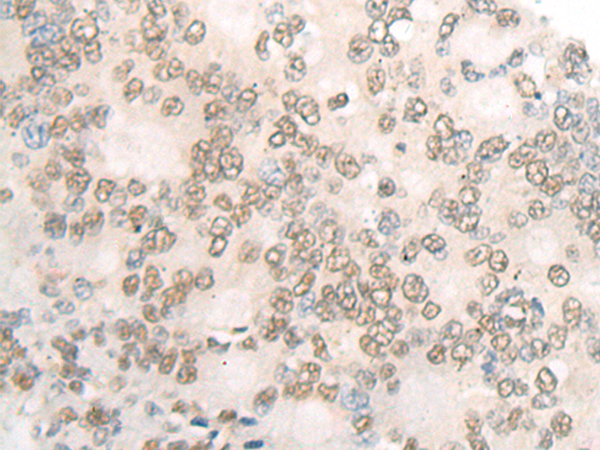

分类: 科研抗体货号: P06359别名: C2orf37应用: IHC反应种属: Human, Mouse, Rat